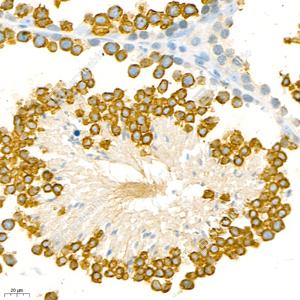

IHC检测Thyroid Hormone Receptor alpha蛋白(货号 GB111289). 样品: 小鼠睾丸, 4%多聚甲醛 (货号G1101) 固定12-24小时. 抗原修复: 柠檬酸抗原修复液(干粉, pH 6.0) (G1201), 98℃, 20分钟. —抗: 1: 1000稀释, 4℃ 孵育过夜. 二抗: HRP标记山羊抗兔IgG (H+L) (货号GB23303), 1: 200稀释, 室温孵育1小时. |